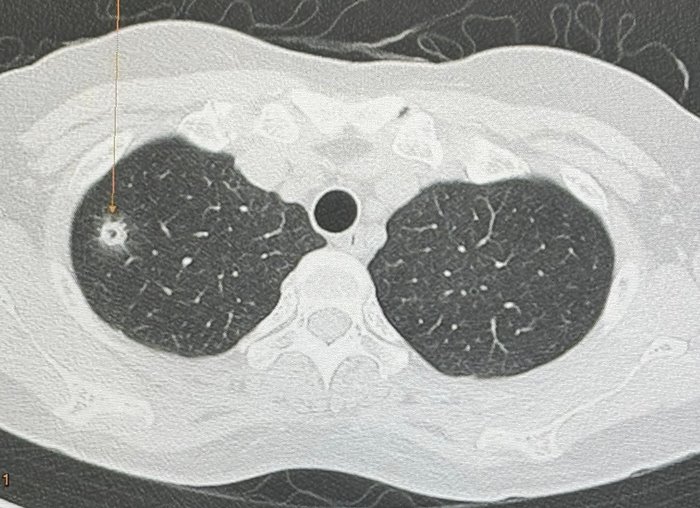

วันที่ 3 มิถุนายน 2567 นพ.มนูญ ลีเชวงวงศ์ แพทย์เฉพาะทางด้านโรคระบบการหายใจ โรงพยาบาลวิชัยยุทธ โพสต์ผ่านเฟซบุ๊ก หมอมนูญ ลีเชวงวงศ์ FC ระบุว่า พบเคสผู้ป่วยหญิงอายุ 52 ปี บ้านอยู่ กทม. ปกติแข็งแรงดี ไม่ไอ ไม่มีไข้ ไม่เบื่ออาหาร น้ำหนักไม่ลด ไม่ปวดหัว ไม่เคยสูบบุหรี่ ไม่มีโรคประจำตัว ไปตรวจร่างกายประจำปี เมื่อ 12 พฤษภาคม ที่ผ่านมา เอกซเรย์ปอดพบก้อนเล็ก ๆ เกิดขึ้นใหม่ที่ปอดขวากลีบบน

เอกซเรย์ปอดก่อนหน้านั้น 1 ปีปกติ ทำคอมพิวเตอร์ปอดพบก้อนขนาด 0.9 × 0.9 × 1.7 เซนติเมตร เห็นโพรงอยู่ข้างในก้อนที่ปอดขวากลีบบน ตรวจเลือดไม่ติดเชื้อเอชไอวี